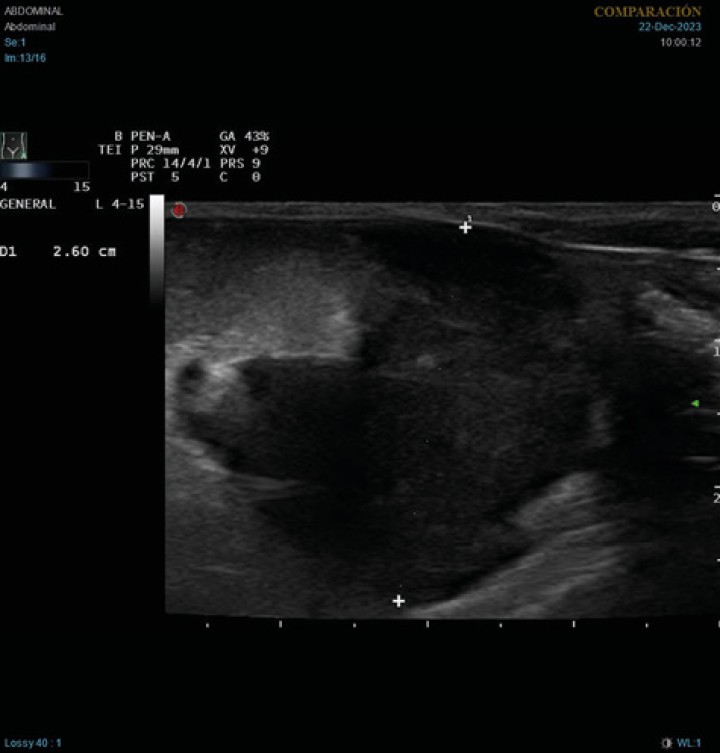

En la ecografía abdominal se observó esplenomegalia con parénquima heterogéneo, linfadenopatía abdominal generalizada y una masa hipoecoica de 2,6 cm de diámetro en la zona de proyección de los linfonodos mesentéricos (Fig. 1). También se observaron hallazgos ecográficos compatibles con peritonitis, como aumento de la ecogenicidad difusa del peritoneo y presencia de líquido libre anecoico, en este caso no puncionable. Por cuestiones económicas los tutores rechazaron ampliar los análisis sanguíneos con un proteinograma.

Figura 1

Imagen ecográfica longitudinal del abdomen caudal. Masa heterogénea, principalmente hipoecoica, de 2,6 cm de diámetro, con hiperecogenicidad de la grasa adyacente.